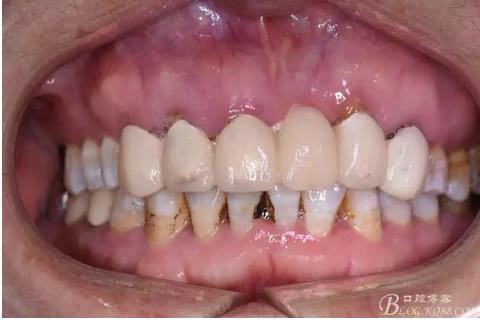

圖3.術前口內正面照:12前庭溝輕度捫痛、有乒乓感